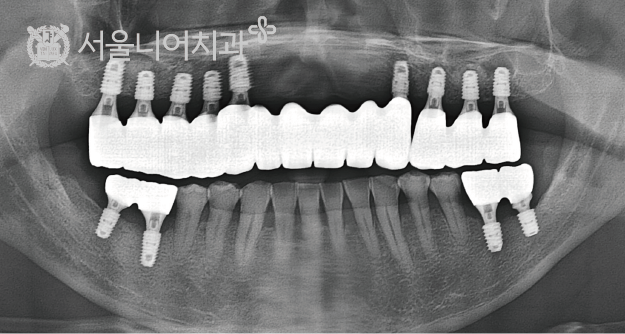

before & after

꼭 필요한 치료만을 권해드리는 서울니어치과의 임플란트 시술 사례

before

after

case 5. 70대 남성 / 잇몸병으로 상실된 다수 치아 / 오스템 SOI 임플란트 8개 / 뼈이식

꼭 필요한 치료만을 권해드리는

서울니어치과의 임플란트 시술 사례

case 1. 전악 임플란트

case 2. 전악 임플란트

case 3. 전악 임플란트

case 4. 전악 임플란트